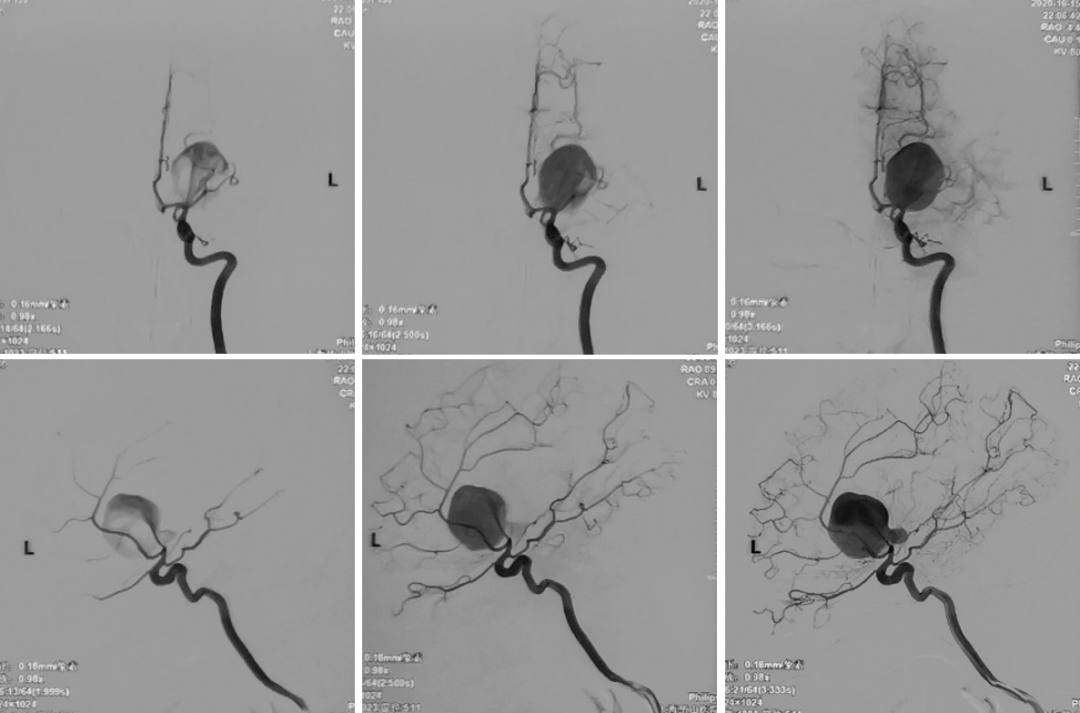

性别:女性,年龄:33 y.o

20分钟无明显神经功能障碍

加强试验:无症状

术前诊断: